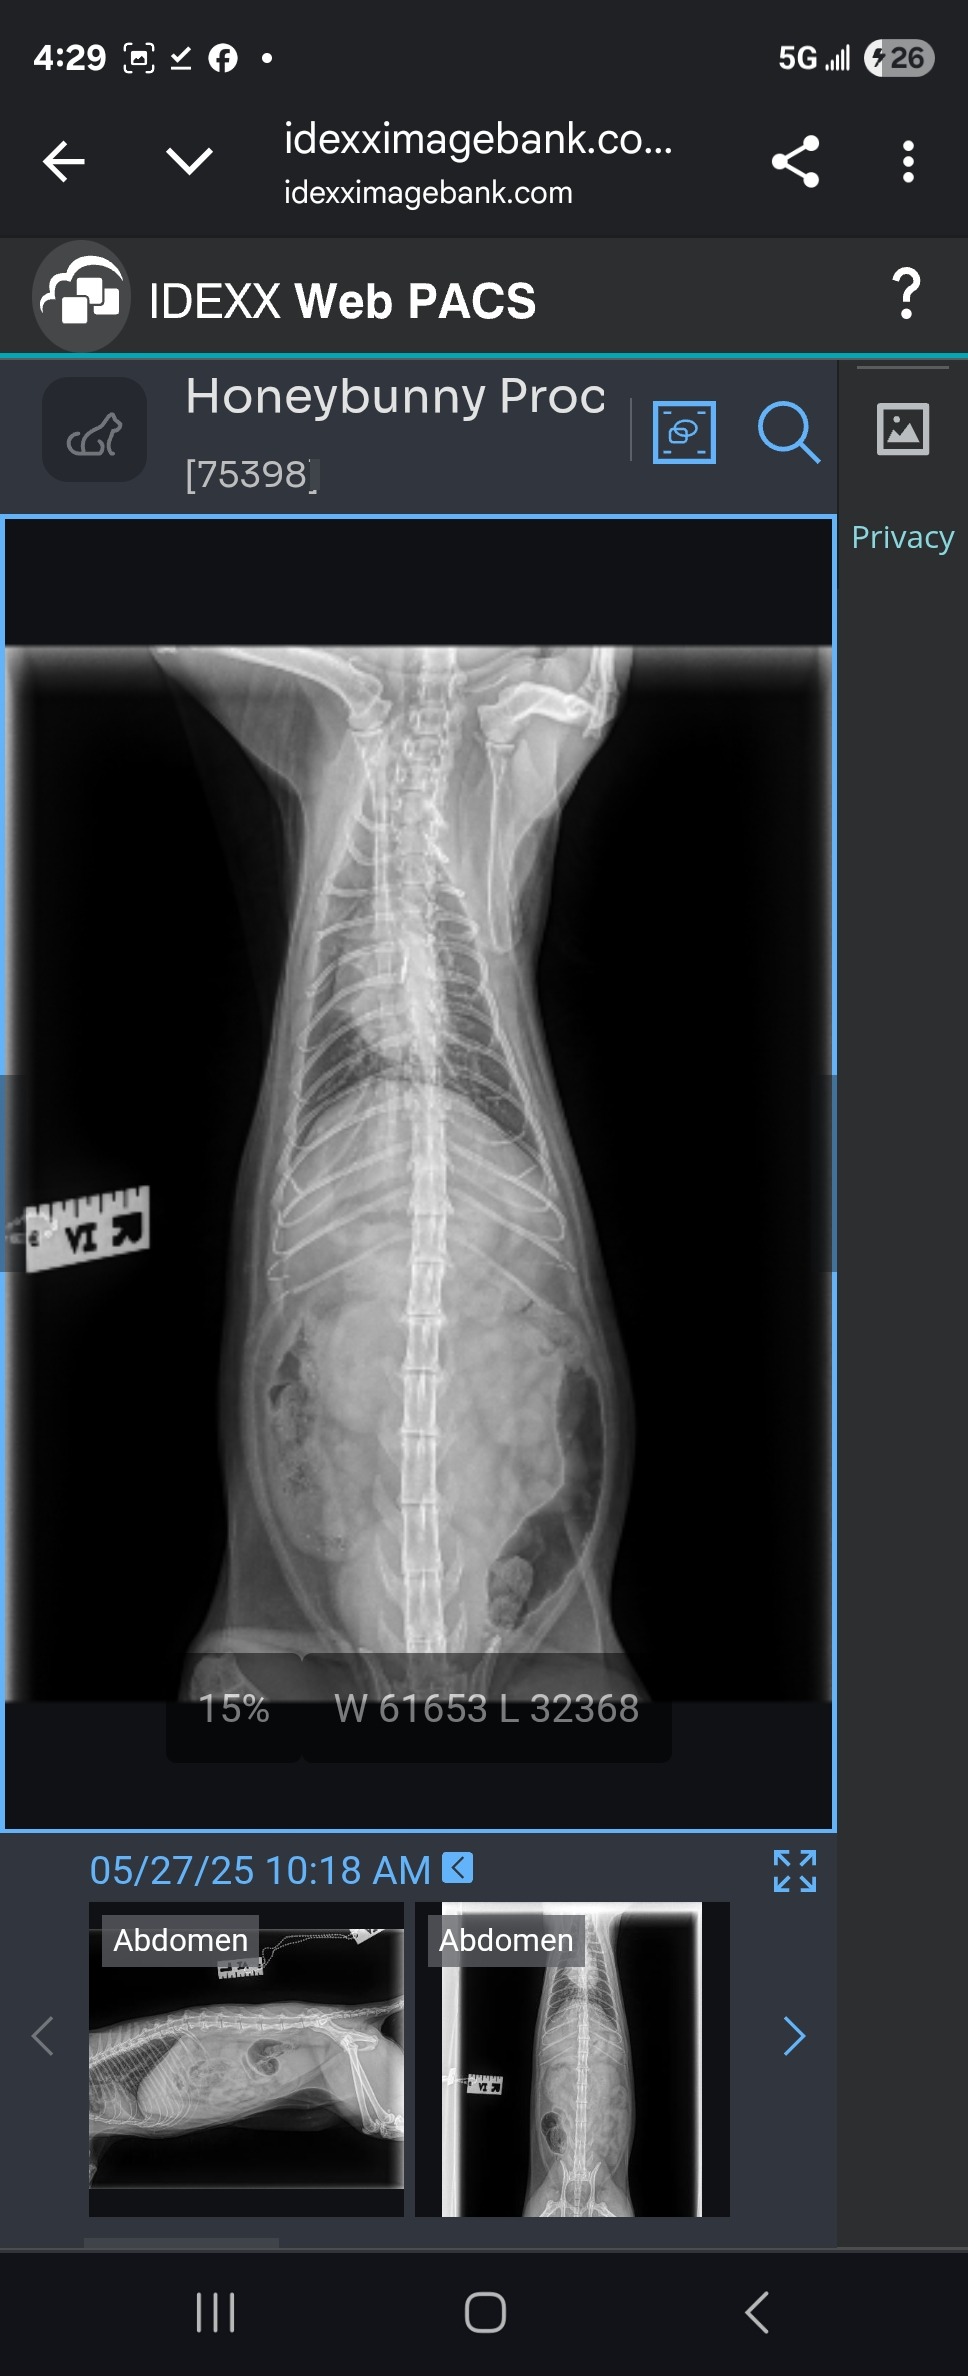

My cat Honeybunny has an obstruction in her intestines and needs surgery to survive.

A few days ago she started vomitting & having diahrrea. I took her to the vet, and they did full tests and xrays, and found she has a foreign substance in her intestines and its not moving. The vet said it could be hair or something else, but ive never known her to eat anything she shouldnt - not threads or paper or anything at all. I went back the next day for another xray to see if it had moved at all and it hadnt.

I am going back again today, and if the mass still hasnt moved, the only option is surgery, which is 4-5k.